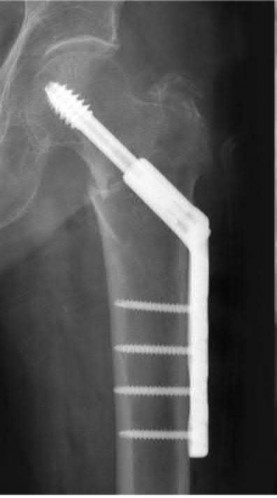

Question 2:

A 28-year-old male sustains a severe hyper-dorsiflexion injury to his ankle in a motor vehicle accident, resulting in a Hawkins Type III talar neck fracture. Which of the following arteries provides the predominant blood supply to the body of the talus, placing it at significant risk for avascular necrosis in this injury?

The artery of the tarsal canal, which is a branch of the posterior tibial artery, provides the dominant blood supply to the talar body. In a Hawkins Type III fracture (talar neck fracture with subtalar and tibiotalar dislocation), the blood supply from the artery of the tarsal canal, the artery of the sinus tarsi, and capsular vessels are disrupted, leading to an avascular necrosis (AVN) rate approaching 100%.